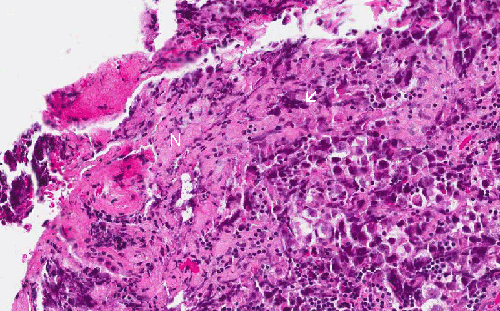

Hematoxylin & eosin

Area 1: The pink substance indicate the necrotic tumor tissue (N). The very dark blue, elongated material are nuclei with crush artifacts (arrow).

• The tumor is highly cellular. The blood around the tumor is more likely due to the procedure than genuine hemorrhage. In some areas of the tumor, there is some necrosis which appears as pink, amorphous substances (Area  1).

This medium-magnification photo shows the intermingled relationship between the neoplastic germinoma cells and the reactive lymphocytes.